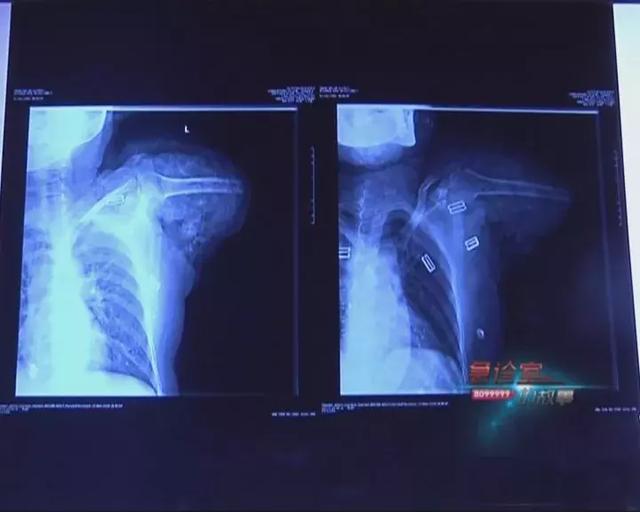

相比起躺在ICU里的小周,失去左臂的张大姐,52岁的姚大姐是不幸中的万幸。她在昭通永善老家使用磨面机时,她的右手被卷入皮带,瞬间手臂断成两截。

从昭通老家赶到云南骨科医院急诊室已经是晚上10点20,凌晨2点40就被推上手术台,第二天上午8点40才下手术,6个小时里,医务人员竭尽全力与“死神”赛跑。

云南骨科医院修复重建显微外科中心 医生 唐炼:“患者情况是非常危重的,手腕部完全离断,上部绝大部分都断了,神经被抽了出来 ,连着一点组织,现在一期手术没有出现感染,比较顺利,两边的都断了还能接起来,就是非常给出幸运的。”

如今,姚大姐一天天恢复,断成两截的右臂也慢慢了有知觉。